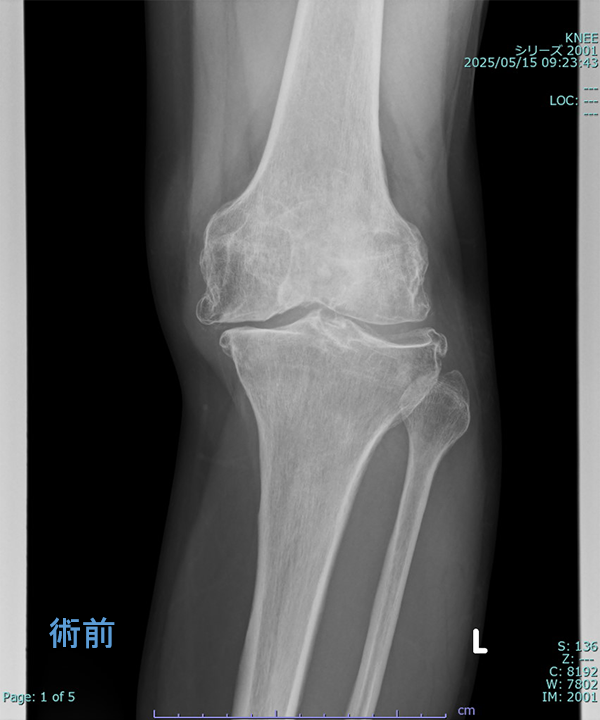

変形性膝関節症に対する手術

◆人工膝関節全置換術

(Total Knee Arthroplasty:TKA)

入院期間 3~4週間

外来リハビリ 2~3か月

術前